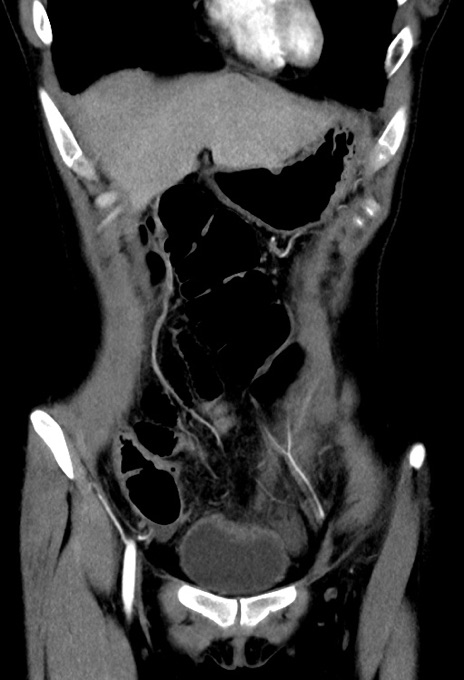

症例17(冠状断像)

【症例】20歳代女性

【主訴】嘔吐、下腹部痛

【現病歴】昨日夕食後に嘔吐し下腹部痛が出現。本日になっても嘔吐持続し改善しないため来院。

【身体所見】意識清明、BT 37.2℃、BP 108/67mmHg、腹部:平坦、やや硬、下腹部正中から右にかけて圧痛あり、反跳痛軽度あり、tapping pain(+)。

【データ】WBC 13600、CRP 14.94